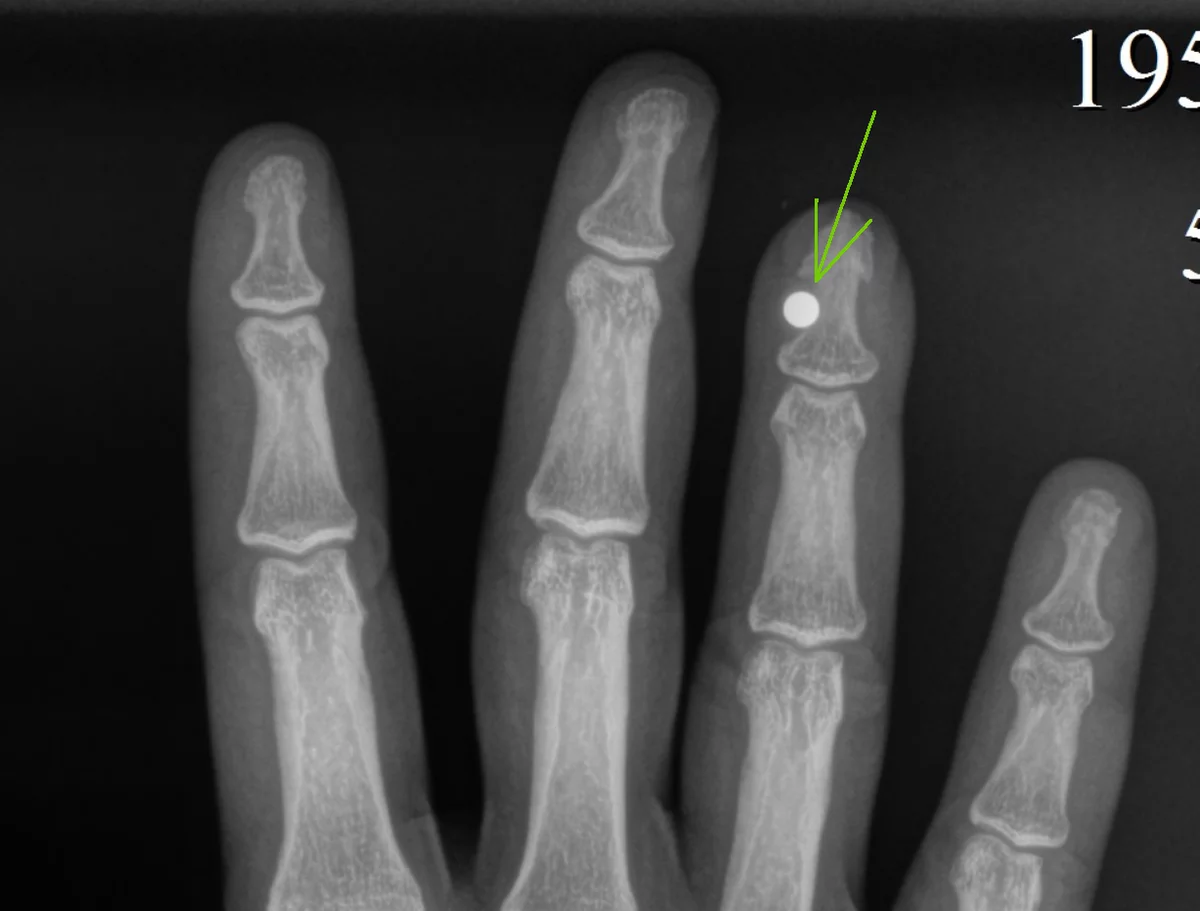

Магнит на рентгене, принадлежит zen.yandex.ru/media/id/592f4526d7d0a6f53d9a37de/magnit-v-palce-kak-eto-5a6ad7c21aa80c976bd2c4d3

В чем суть? Если кратко, то вам вшивают хирургическим путем в палец(можно и любую другую часть тела, но палец это то, чем мы можем достаточно легко двигать, к тому же подушечки пальца весьма чувствительны) ма-а-аленький магнит, покрытый любым биосовместимым материалом, который не отвергнет организм.

Как это работает? Тут совсем несложно. Магнит реагирует на электромагнитные волны и издает вибрации которые вы ощущаете нервными окончаниями пальца. А еще вы сможете пальцем поднимать небольшие металлические предметы, монеты, крышки, винтики